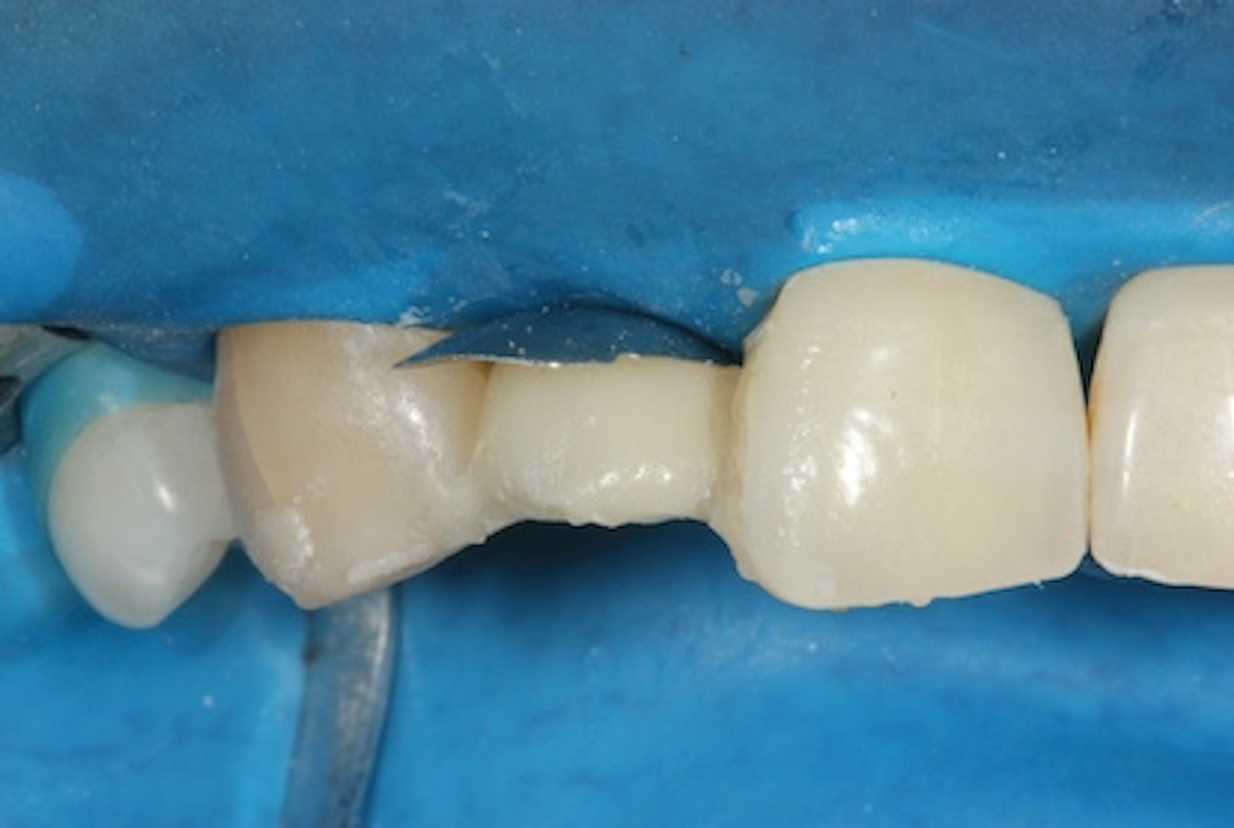

(1.) Pretreatment radiograph of tooth No. 7 showing an internal resorption lesion.

Figure 1

Depending on whether patients present with an existing edentulous space or a non-restorable tooth requiring extraction, as well as other factors, their long-term treatment goals may vary. Nonetheless, each case should be evaluated to identify patients' needs regarding immediate restoration. In the example case presented here, a radiographic examination of a discolored canine lead to the discovery of a lateral incisor (tooth No. 7) with internal resorption that required extraction (Figure 1). The tooth was extracted, and an implant was subsequently placed (Figure 2); however, the patient would be unable to complete the treatment for an extended period of time, so a fiber-reinforced composite bridge was chosen to serve as an ideal long-term provisional replacement option.